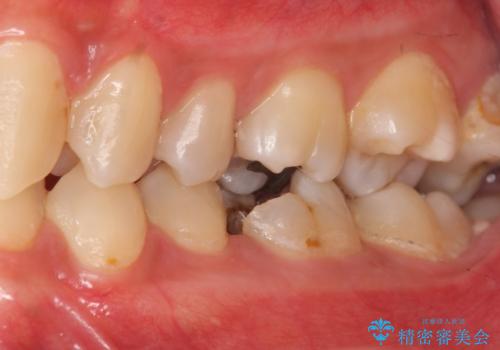

放置した虫歯の治療 親知らずの手前が虫歯

- 詰め物が取れて放置していたとのこと。

虫歯が大きかったため、被せ物(クラウン)としました。

親知らずを抜いてから治療しています。

幸い神経を取らずにすみました。